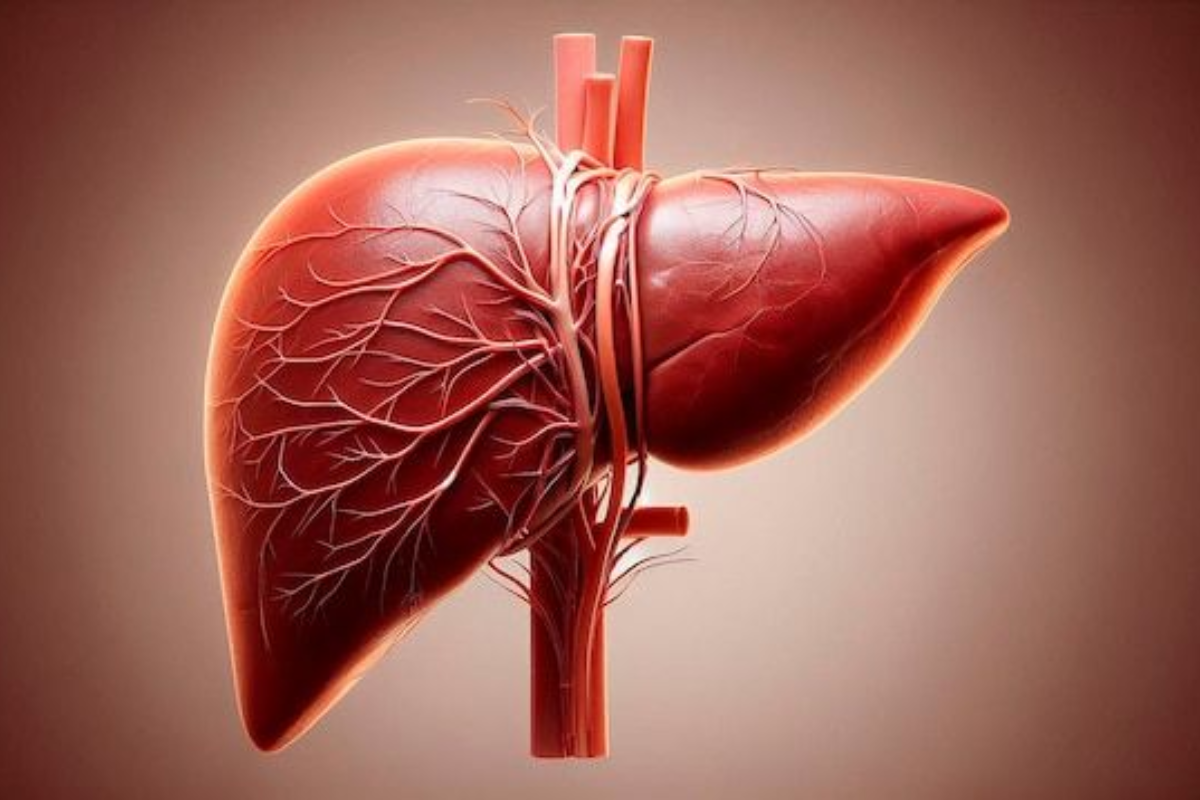

3. Heart and Liver Health: दिल का सबसे करीबी है लिवर

लिवर को शरीर का मेटाबॉलिज़्म सेंटर कहा जाता है. यह शरीर की सफाई, पाचन, पोषण का वितरण और हार्मोनल बैलेंस जैसे 500 से भी ज्यादा काम करता है. जब लिवर फैटी हो जाता है, तो खून की गुणवत्ता और लिपिड लेवल बिगड़ने लगते हैं. इससे शरीर में खराब कोलेस्ट्रॉल (LDL) बढ़ जाता है और अच्छे कोलेस्ट्रॉल (HDL) का स्तर घट जाता है.

ऐसे में दिल की धमनियों पर दबाव पड़ता है और हृदय रोग की संभावना बढ़ जाती है.